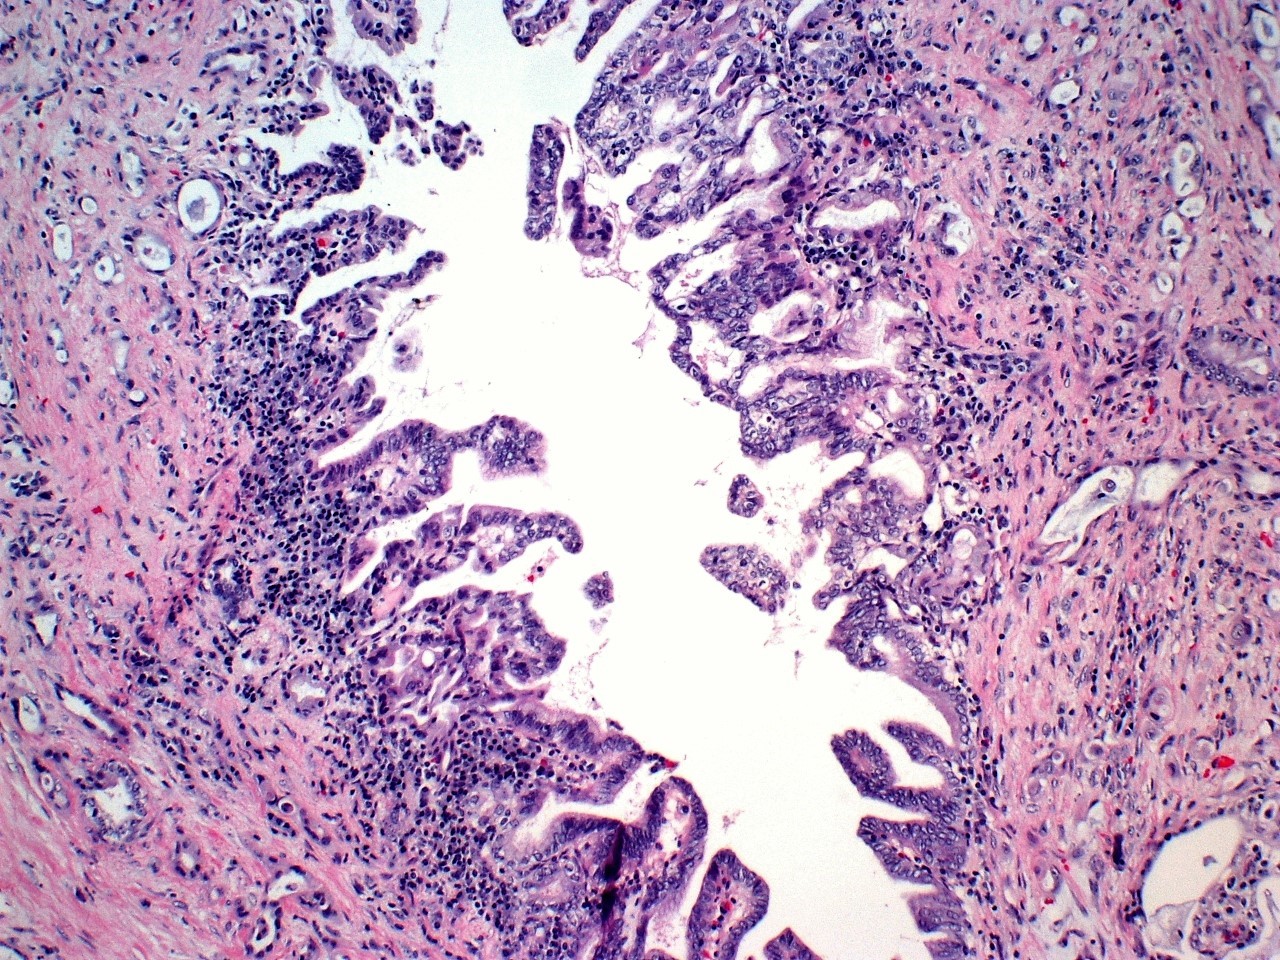

Case history:

A 14-year-old girl presented with left hip pain. Imaging studies show a...